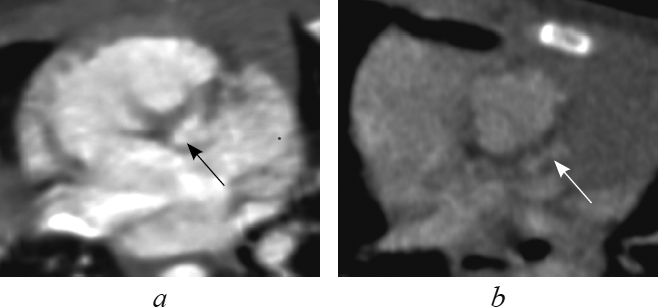

Анатомические признаки ушка, характерного для морфологически левого предсердия (узкая вытянутая форма с заостренным концом, узкое соединение с предсердной полостью, хорошо выраженная дольчатость [1, 2, 4, 16]), определяют в реформации левых камер сердца (рис. 2). В этой реформации обращает на себя внимание соединение морфологически левого предсердия с морфологически левым желудочком при транспозиции (рис. 2, а), соединение морфологически левого предсердия с морфологически правым желудочком при корригированной транспозиции (рис. 2, b).

Рис. 2. В реформации левых камер сердца ушко морфологически левого предсердия при транспозиции магистральных сосудов (а, стрелка), при корригированной транспозиции магистральных сосудов (b, стрелка)

Fig. 2. Left heart chambers reformation. The eyelet of the morphologically left ventricle in great arteries transposition (a, arrow) and in corrected great arteries transposition (b, arrow)